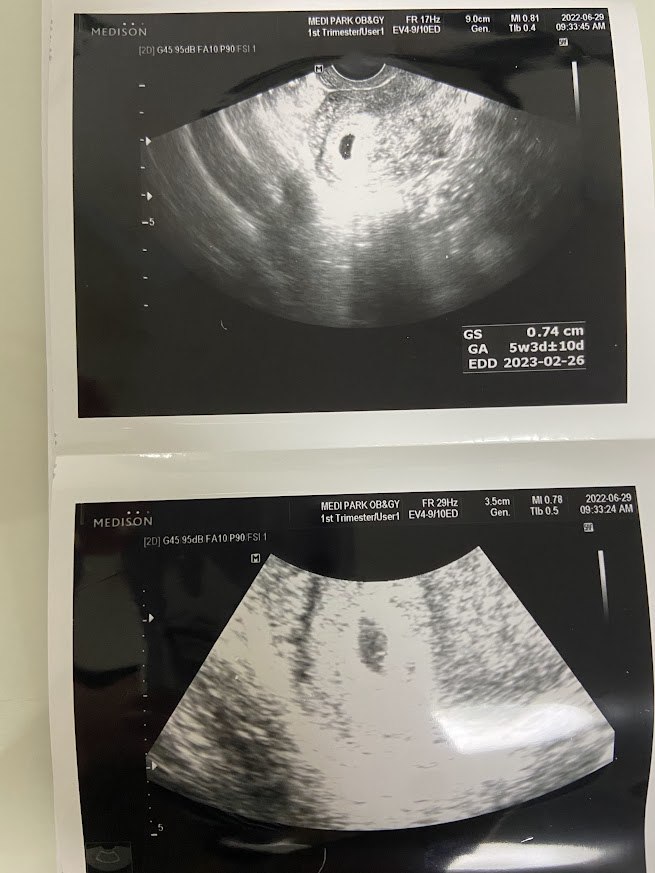

1cm도 되지 않는 아기집, 그리고 공식 서류

그로부터 며칠 뒤에는 초음파를 보러 산부인과에 갔다. 둘이 같이 산부인과에 온 건 이번이 처음. 남편도 나도 뭔가 어색했지만 병원에서 워낙 친절하게 잘 설명해 주셔서 금방 마음이 편안해졌던 기억. 하지만 초음파 결과 내 예상대로 아직은 너무 작아서 임신 '진단'을 내리기가 어렵다고. 원래라면 2주 뒤에 다시 와야 하는데 그전에 우리는 출국하기 때문에 출국 직전 한 번 더 오기로 예약하고 병원을 떠나려는 순간, 수납하고 나니 데스크에서 서류를 한 장 준다. 이게 뭔가 했더니만 병원에서 임신을 확인해 주는 서류. 이걸 가지고 국민행복카드 바우처를 신청할 수 있다고 했다. (아니 선생님 아직 임신이라고 확정하기 어렵다고 하셨는데요....!) 여하튼 임신 확인이 된 이후 바우처를 신청하면 바우처 금액 내에서 임신/출산 관련 진료비를 쓸 수 있는 것! 대한민국 만세!

그 후 두 번째 방문에서 난황을 확인했고, 준비성이 뛰어난 (= 원체 걱정이 많은) 나는 미리 입덧약을 처방해 달라고 말씀드려서 한 통 받아왔다.